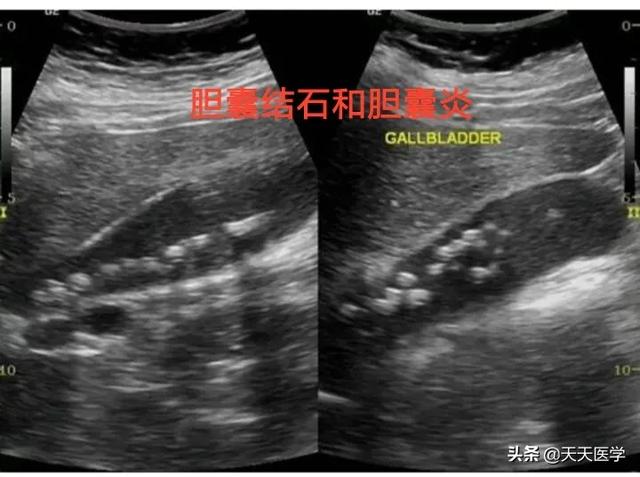

Ci-dessus, une échographie montrant la présence de plusieurs calculs de taille variable dans la vésicule biliaire.